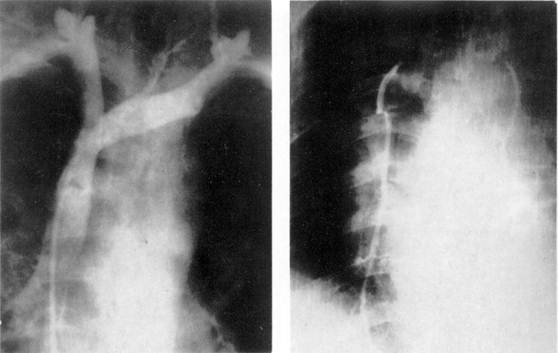

Рис. 3. Рак верхней доли левого легкого.

а — прямая рентгенограмма: б — боковая рентгенограмма.